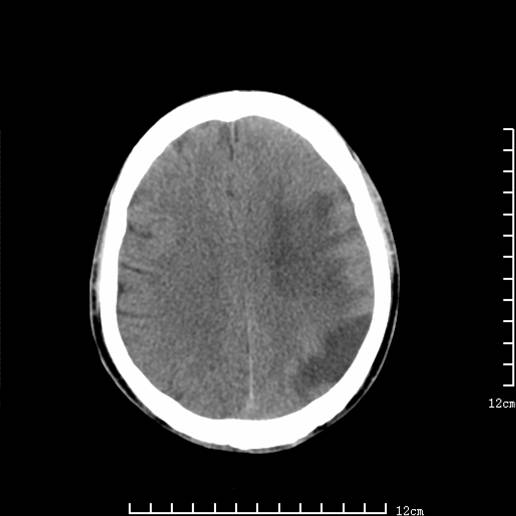

以下图像分别是3月25日凌晨及下午图像、3月27日、4月16日的ct图像。

3月27日

大脑中动脉供血区大面积脑梗塞没有问题。

支持左侧大脑中动脉分布区脑梗塞。